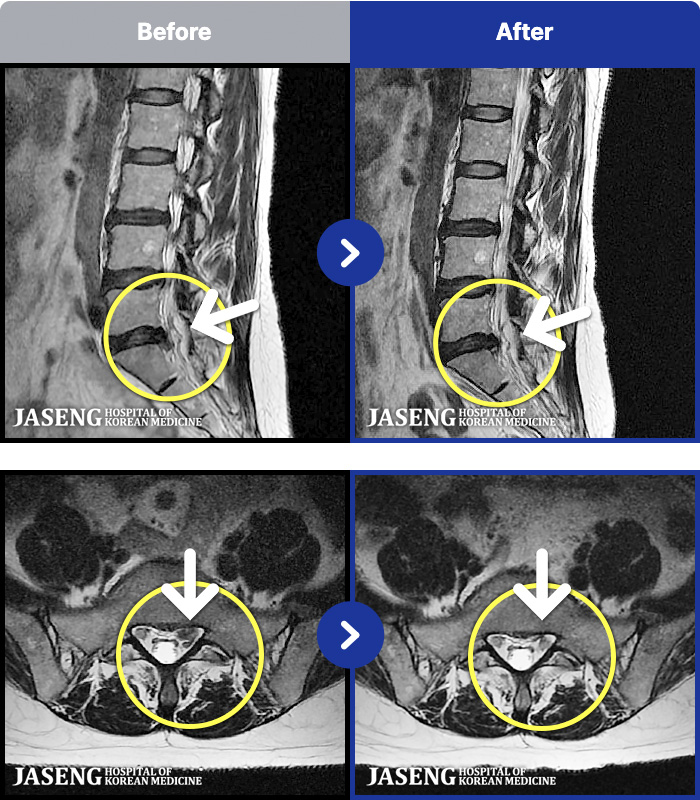

MRI ġ

54 MRI ũ ʸ Ȯϼ.

54

[Կñ:22.04.11~22.07.28]

[_㸮ũ] Ͽ ü Ÿ Ͽϴ.